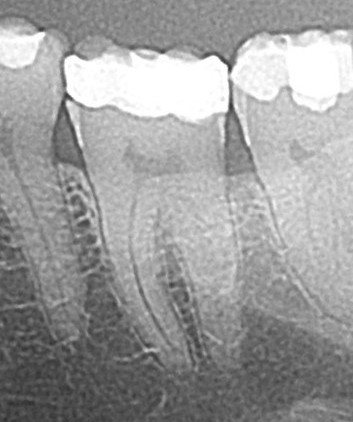

Regenerativni parodontološki zahvat kojim se kirurškim putem regenerirao infrakoštani defekt(parodontološki džep)